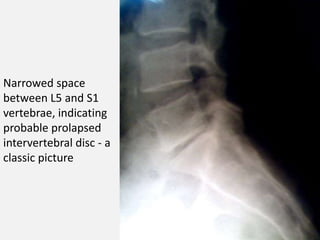

X-Ray : lumbo-sacral spine;

 Narrowed disc spaces.

 Loss of lumber lordosis.

 Compensatory scoliosis.

Narrowed space

between L5 and S1

vertebrae, indicating

probable prolapsed

intervertebral disc - a

classic picture